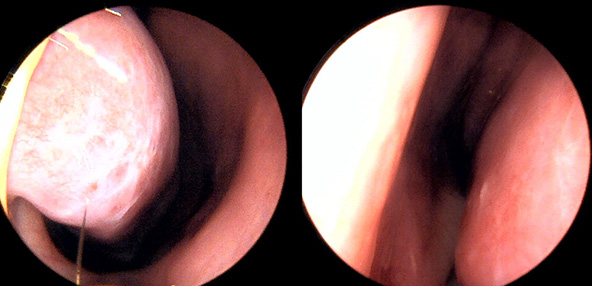

※ 비중격 비염 수술 후 생길 수 있는 부작용으로는 출혈, 감염, 염증이 있을 수 있습니다.

본 사진은 의료기관에서 진료를 본 환자이고, 전후 사진 인물이 동일인이며,동일조건에서 촬영이 되었습니다.